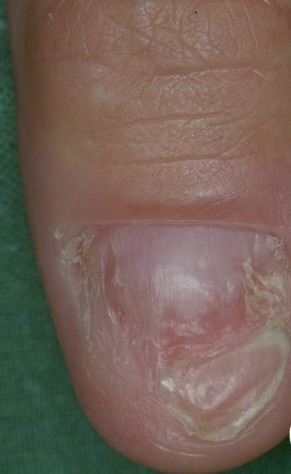

• Solitary glomus tumors have the following characteristics:

• Blue or purple

• Papules or nodules that can be blanched

• Size usually smaller than 1 cm

• Located most commonly in acral areas, especially subungual areas of fingers and toes